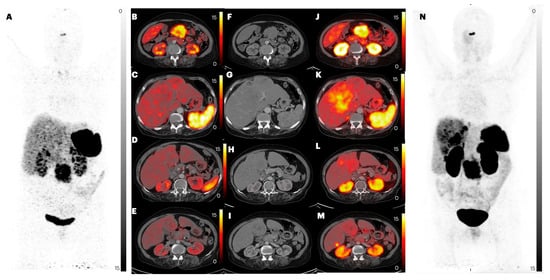

2.2.4. Liver Metastases

| Parameters | Imaging Method | Primary | Lymph Node Metastasis | Lung Metastasis | Liver Metastasis | Bone Metastasis |

| Lesion-based analysis | ||||||

| CT | 47 | 107 | 12 | 283 | 41 | |

| [68Ga]Ga-DOTANOC | 40 (85.1%) | 82 (76.6%) | 0 (0%) | 253 (89.4%) | 34 (82.9%) | |

| [68Ga]Ga-DATA5m-LM4 | 42 (89.4%) | 83 (77.6%) | 0 (0%) | 292 (value greater than CT) = 100% | 45 (value greater than CT) = 100% | |

| p-value | 0.544 | 0.862 | - | <0.0001 | 0.005 | |